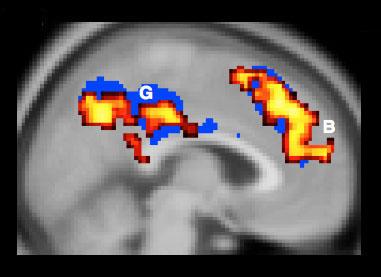

Figuring he had a clever way to prove it physiologically, he and his team compared the brain scans of people who judged active harm to be worse than passive harm to the scans of people who judged them as morally equal. His assumption was that those who saw a moral difference did so by explicit reasoning. Such people should therefore have exhibited greater activity in the dorsolateral prefrontal cortex than those who saw no moral distinction. But to Cushman’s surprise, the greater levels of DPFC activity lay with those who saw active harm and passive harm as morally the same.

“The people who are showing this distinction are actually the ones who show the least evidence of deliberative, careful, controlled thinking,” he said, “whereas the people who show no difference between actions and omissions show the most evidence of careful deliberative controlled thinking.”